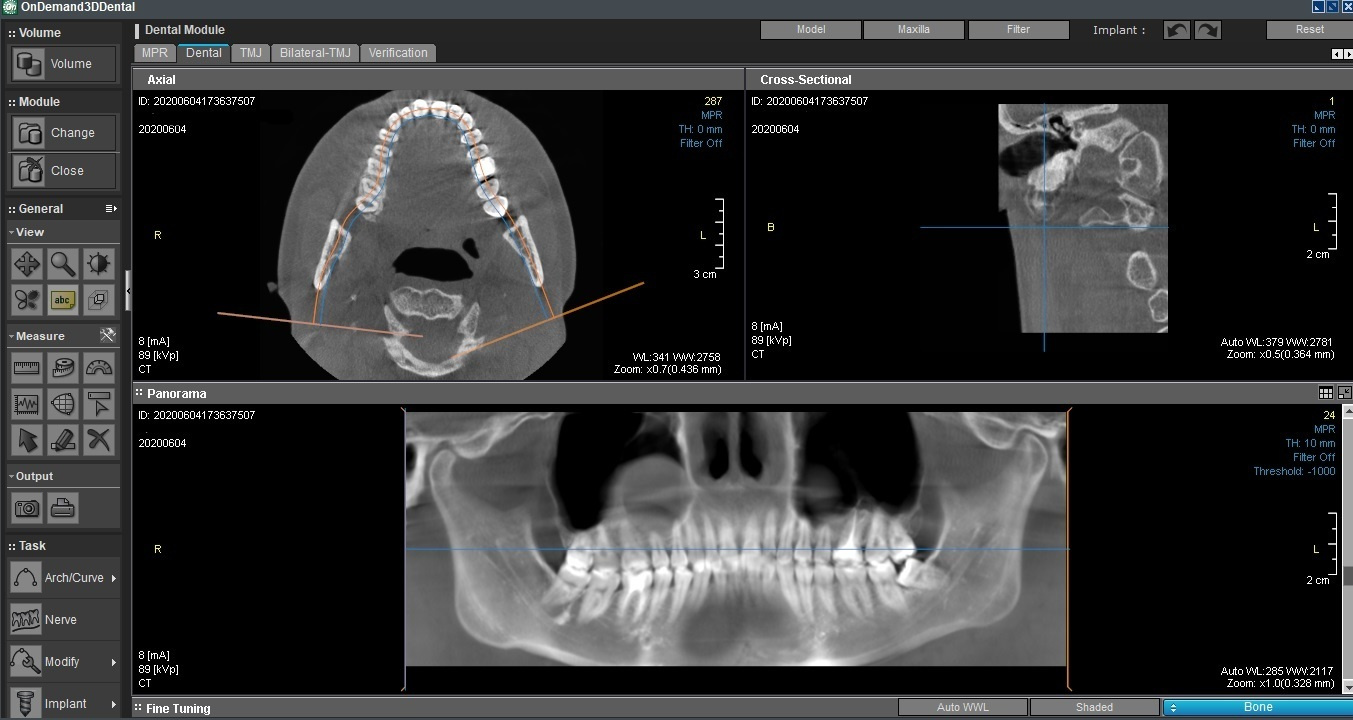

Компьютерная томография (КТ)

Ортопантомограмма (ОПТГ), «выделенная» из КТ в специальной программе